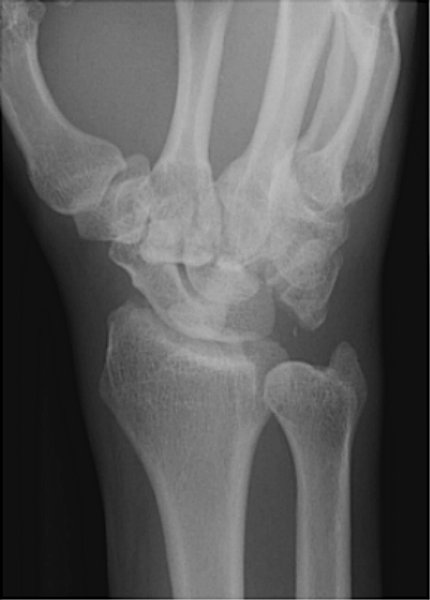

Return to Lunate Dislocation